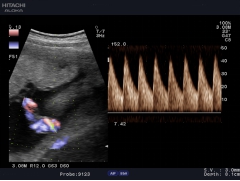

實時三同步

B型、彩色和頻譜多普勒三種模式同時實時顯示,獲得更精確地采樣定

位,更直觀進行對比分析。